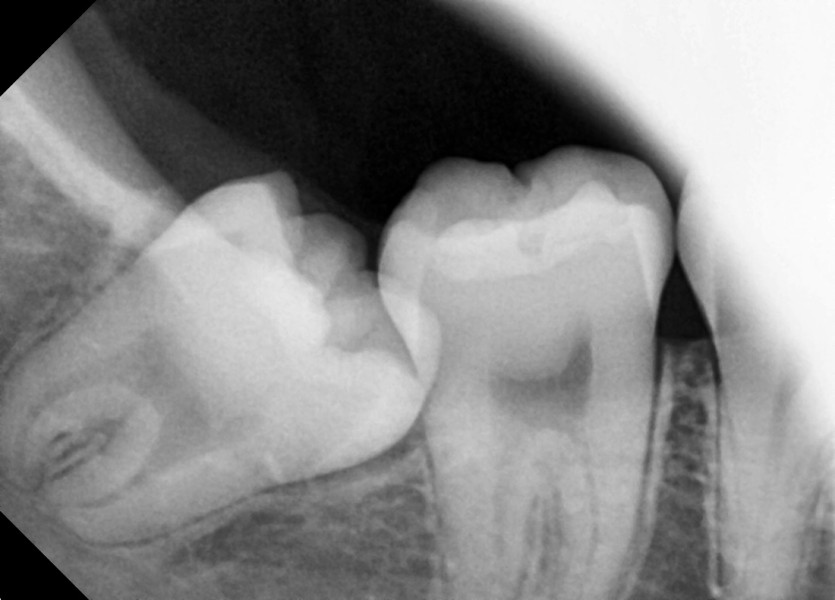

#48 사랑니 발치

구강외과 전문의가 당일 발치했습니다.